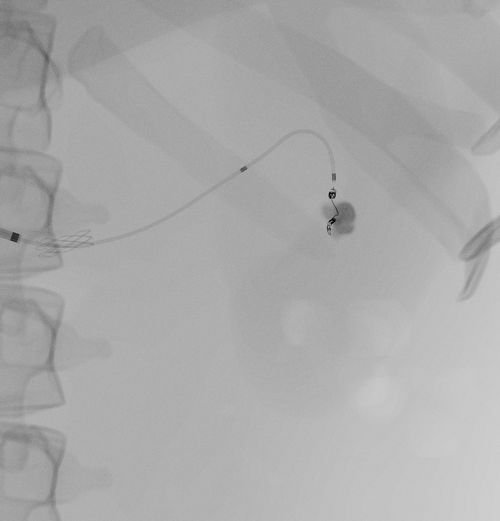

• Possibility to trigger artery perforation by guide wire mis-manipulation causing bleeding

• Manage renal bleeding using embolization coils